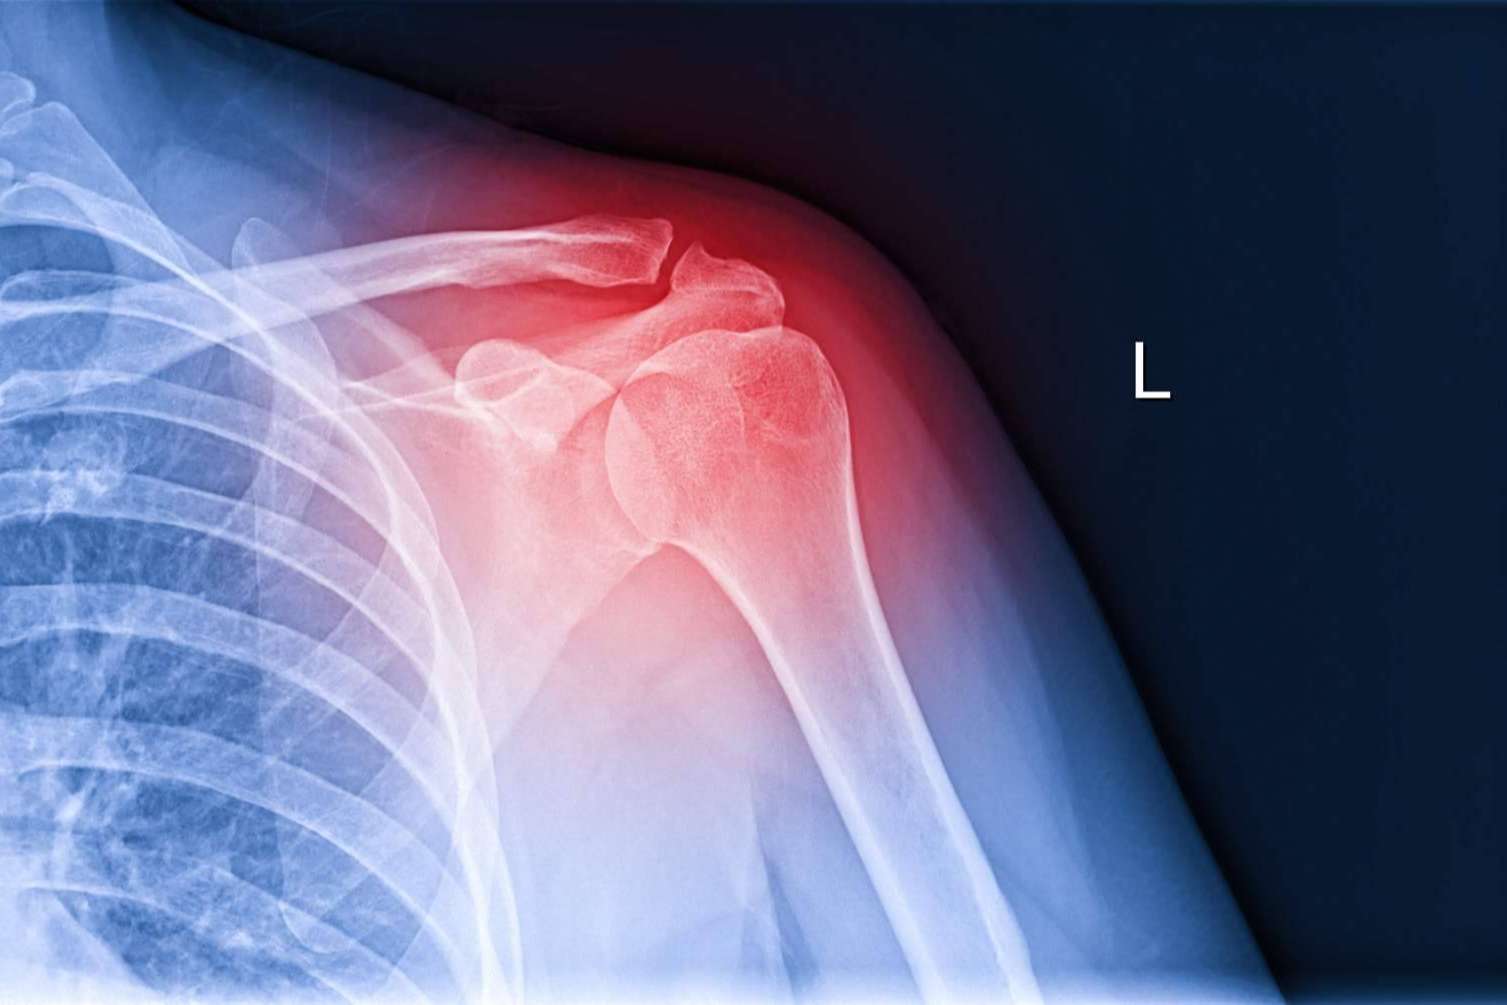

Adicionalmente, realiza una exploración física para valorar la movilidad del paciente y la estabilidad de los tendones. Dependiendo de los resultados de dicho procedimiento, puede solicitar radiografías, ecografía o resonancia magnética para obtener una visión más amplia del problema. Todos estos aspectos le ayudarán a tener un diagnóstico preciso para luego suministrar el tratamiento indicado para cada paciente.